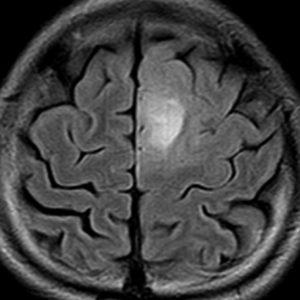

左上前頭回のびまん性グリオーマ diffuse glioma です。手術でほぼ全摘 gross total removalして54グレイの放射線治療とテモゾロマイド化学療法をしました。病理診断は,oilg 2陽性,1p/19q染色体の欠失はない退形成性乏突起星細胞腫 グレード3とされました。全体的にはグレード2であるとの病理医の意見もありましたし,当時は北大病院でもIDHの正確な分子病理診断は行われていませんでした。

5年後です。上前頭回の病巣は落ち着いていましたが,初回にはなかったはずの場所,脳梁前方に急激な再発増大を生じました。また手術で全摘出 gross total removalして,かなり絞った領域に60グレイの放射線治療とテモゾロマイド,アバスチンの投与をしました。病理診断は,IDH wild-tpye, 1p/19q non-codel, MIB 40%, ATRX positive, MGMT negativeの膠芽腫でした。

その後またしばらく寛解継続できました。